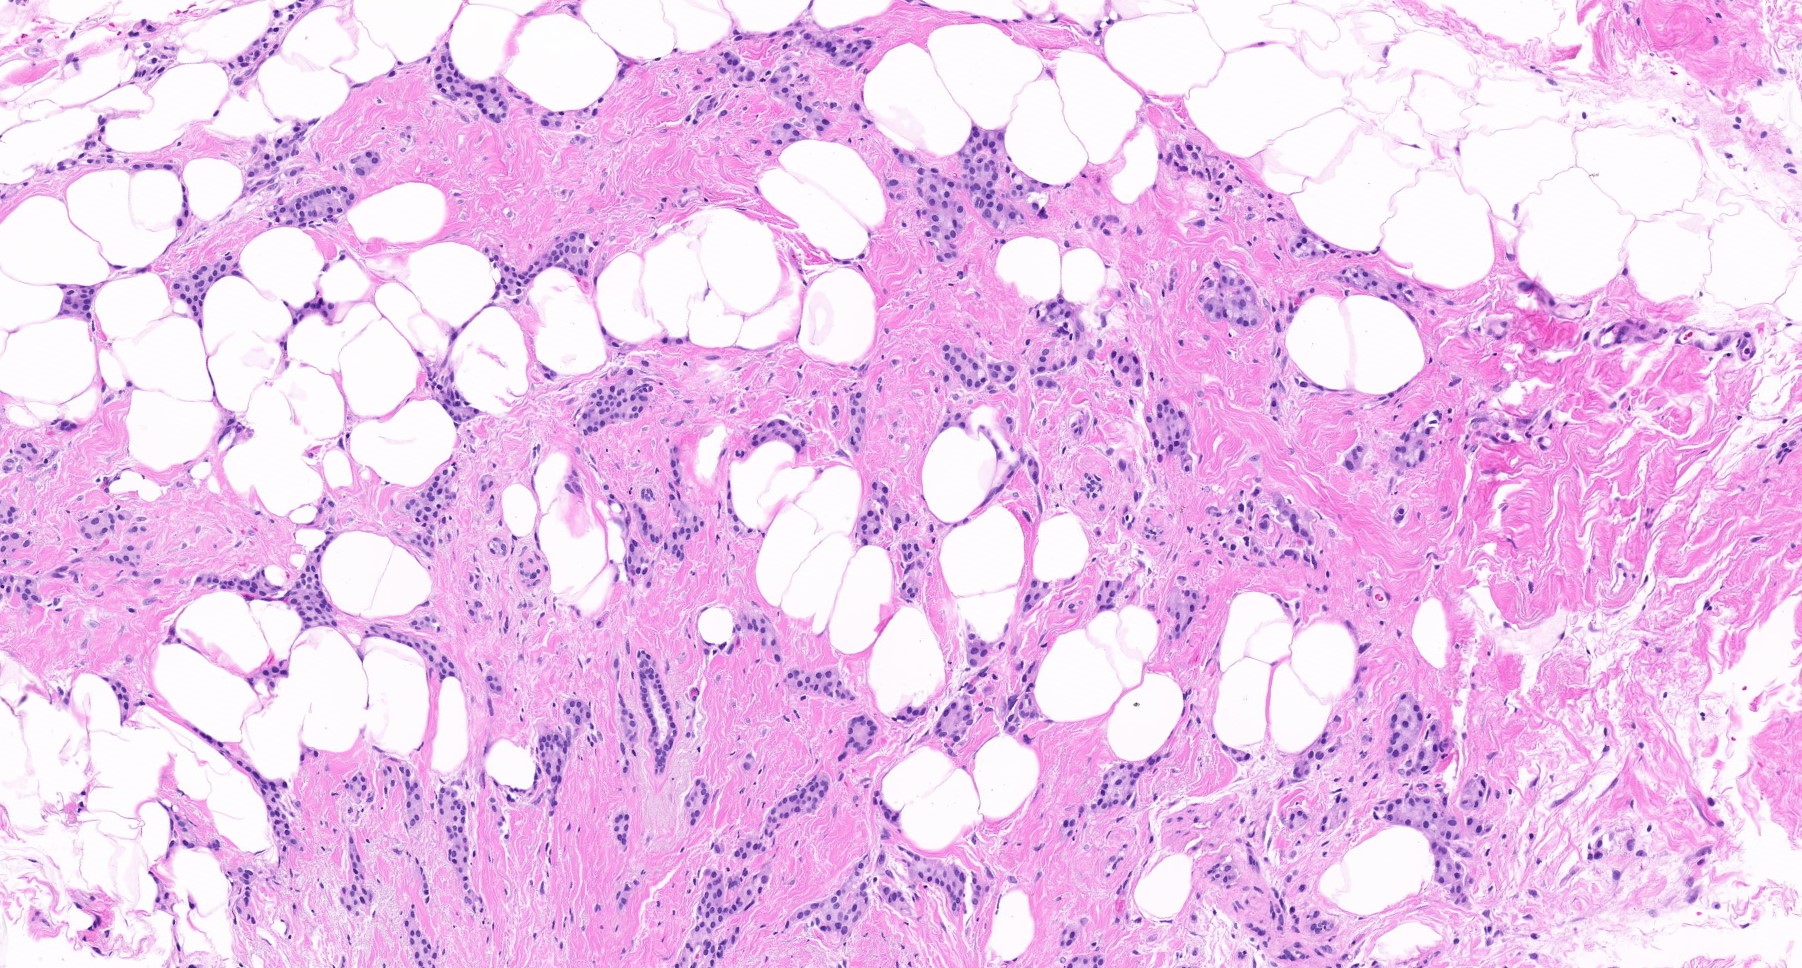

Microscopic (histologic) description

- Histological features of IBC NST vary considerably from case to case and even within the same case

- Margins vary from highly infiltrative, permeating the surrounding tissue, to continuous pushing margins

- Architecture varies from sheets, nests, clusters, cords or individual cells (but lacks the cytomorphological characteristics of invasive lobular carcinoma)

- 2 distinct growth patterns exist:

- Large and solid nests or syncytial infiltrative growth pattern with little associated stroma and an expansive growth that compresses the surrounding stroma (e.g., most basal-like breast cancers)

- Tumors characterized by small cancer nests accompanied by marked fibrosis (desmoplastic / scirrhous); this type diffusely infiltrates the surrounding tissue as an irregular shaped spiculated mass

- Calcification in 60% of cases, variable necrosis

- Elastosis involves stroma, wall of vessels and ducts and causes grossly noted chalky streaks

- Often ductal carcinoma in situ (DCIS) (up to 80%)

Microscopic (histologic) images

Contributed by Julie M. Jorns, M.D., Kristen E. Muller, D.O., Gary Tozbikian, M.D. and Emad Rakha, M.D.